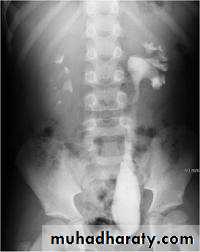

IVU :

- There is rounded or elliptical dilatation of lower end of ureter with thin linear filling defect around it , resembling (cobra head appearance),

- Proximal dilatation of rest of ureter .

- In advanced cases hydronephrosis .

- In obstructed ureterocele , filling defect in the bladder